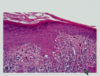

describe the image and what condition it is seen in

psoriasis